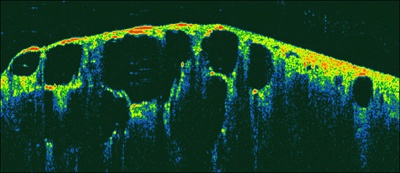

An OCT image showing normal, healthy lung tissue over an aras measuring 4mm x 1.5mm. Credit: Tomophsae/Beth Israel Deaconess Medical Center.